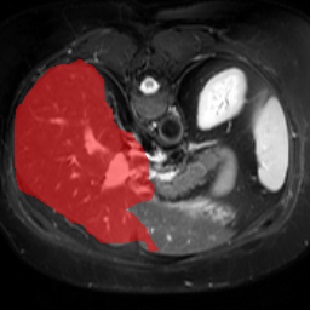

For CMR dataset, we only consider setting 1 because setting 2 is difficult to implement. The results are shown in Table 1 and Figure 4. In general, our proposed method is superior than others. For CHAOS dataset, we consider both setting 1 and setting 2. From the results, we can see the performance of our proposed model is higher than others on CHAOS and CMR datasets. Compared with Q-Net, our mean dice score on CHAOS dataset achieves about 82%. The segmentation results of the model are shown in Figure 5. In setting 2, the slices of the objects containing the test classes are all removed at training stage, and our model still performs well. As can be seen from the Table 2, the segmentation effect of the model on the right kidney is slightly worse than that of ALPNet, but overall, we achieve the best performance. The specific segmentation results are shown in Figure 6. As can be seen from the figure, other methods have excessive segmentation, but ours does not. Our segmentation results are more accurate and reduce redundant segmentation.